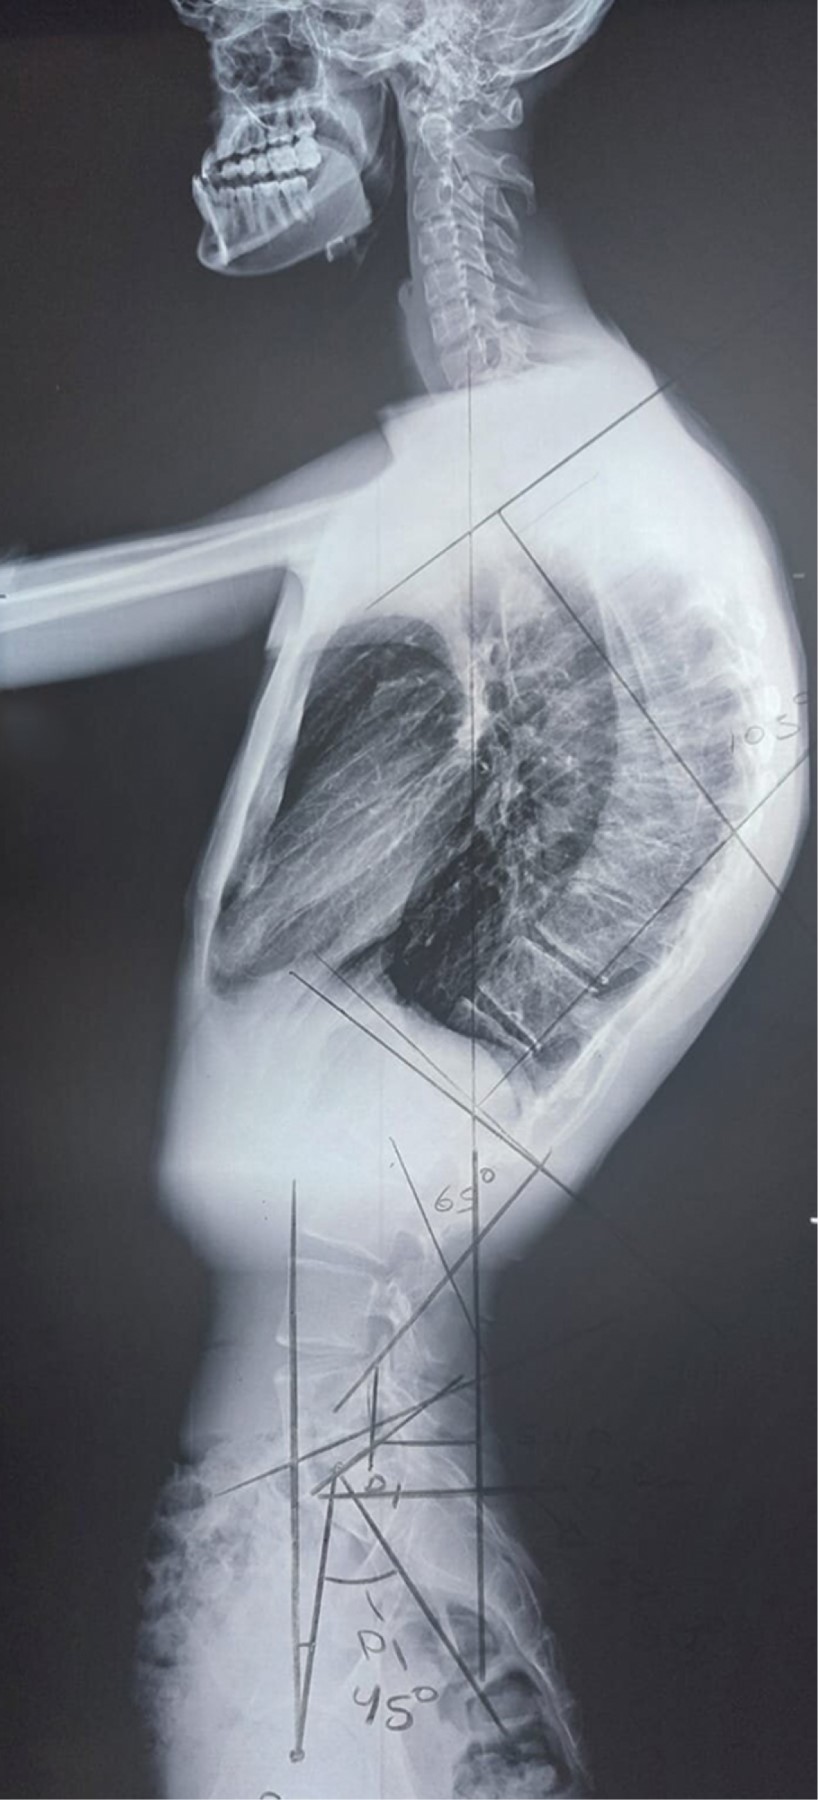

Se presenta caso de paciente masculino de 22 años de edad, el cual es diagnosticado con enfermedad de Scheuermann con una curva torácica de 105°, el paciente muestra madurez esquelética completa, por lo que se propone tratamiento quirúrgico. Esta enfermedad es una patología de constante afrontamiento para el cirujano de columna, por lo que es importante realizar un rápido repaso de la misma y de nuestro accionar como médicos.INTRODUCCIóN

Paciente masculino de 22 años de edad y sin antecedentes de relevancia, el cual se presenta a consulta por deformidad, la cual le crea inseguridad estética y dolor recurrente de región torácica. Se solicitan radiografías anteroposterior (AP) y lateral panorámicas de columna, se detecta una deformidad de 105° de cifosis torácica (Figuras 1 y 2). Se propone al paciente realización de instrumentación posterior y fusión con corrección de curva torácica, quien acepta el tratamiento. Se realiza cirugía de instrumentación y fusión posterior exclusiva de T2 a L2 con tornillos poliaxiales mediante neuronavegación con O-ARM™ y neuromonitoreo (Figuras 3, 4 y 5). El paciente muestra buena evolución inmediata con una pérdida sanguínea menor de 200 ml durante las tres horas de procedimiento quirúrgico, además de buena evolución durante el primer, tercer y sexto mes con desaparición del dolor y corrección de curva a 40°(Figuras 6 y 7).